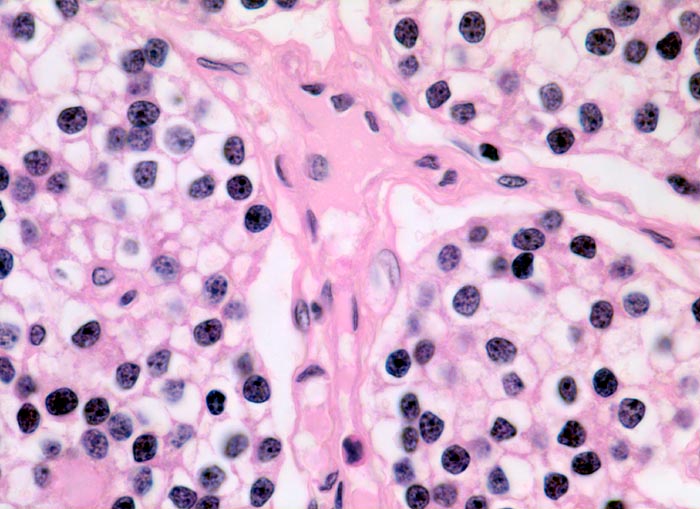

normale Nebenschilddrüse: Hauptzellen

Zu Zellballen angeordnete Hauptzellen. Zwischen den Zellballen verlaufen feine Bindegewebssepten mit Gefässen. Die Hauptzellen bilden das Parathormon. Sie enthalten basophile Granula, Glykogen und Lipide im Zytoplasma. Die Kerne sind rund, das Chromatin ist sehr dicht. Je nach Funktionszustand erscheinen Hauptzellen hell (glykogenreiche wasserhelle Zellen, wenig aktiv) oder dunkel (aktiv).

630